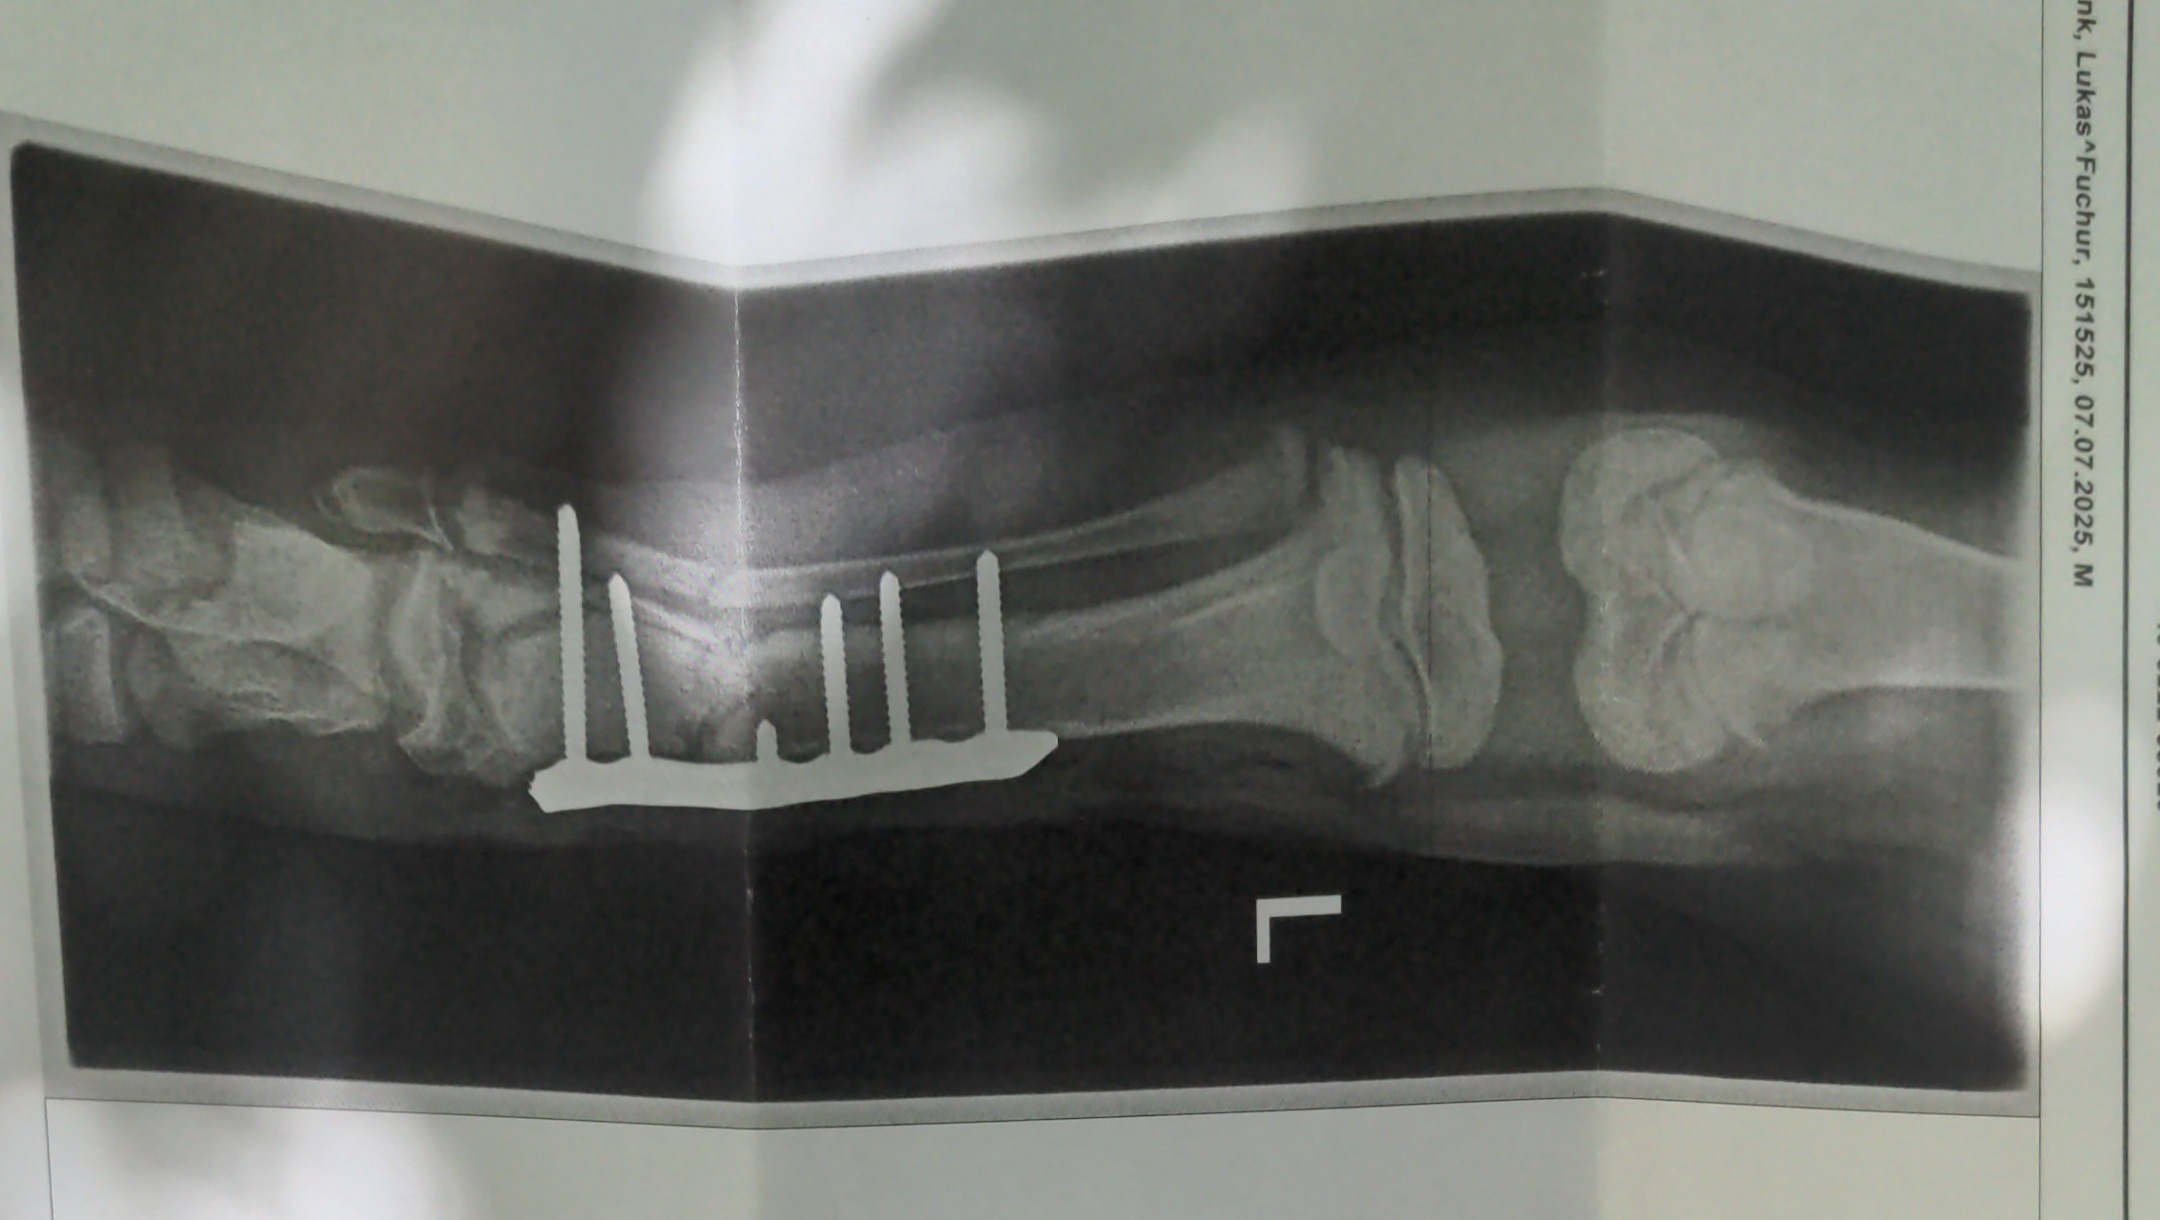

Am folge Tag (19. Sep.) wurde Fuchur in der Tierklinik Wiesloch operiert.

Die OP ist sehr gut verlaufen. Die Bruchstelle wurde mit einer Platte und Schrauben Fixiert.

aktuell ist noch unklar wie sich die Wachstumsfüge unterhalb des Bruches regenerieren wird.

In der dritten Woche nach dem Bruch ist das Wachstum von fuchurs Bein aber glücklicher Weise nach wie vor unaufällig.

Am Montag 06.10. wurden Kontroll-röntgenbilder erstellt und die Fäden gezogen. Der Bruch und die Op Wunde sehen sehr gut aus!!